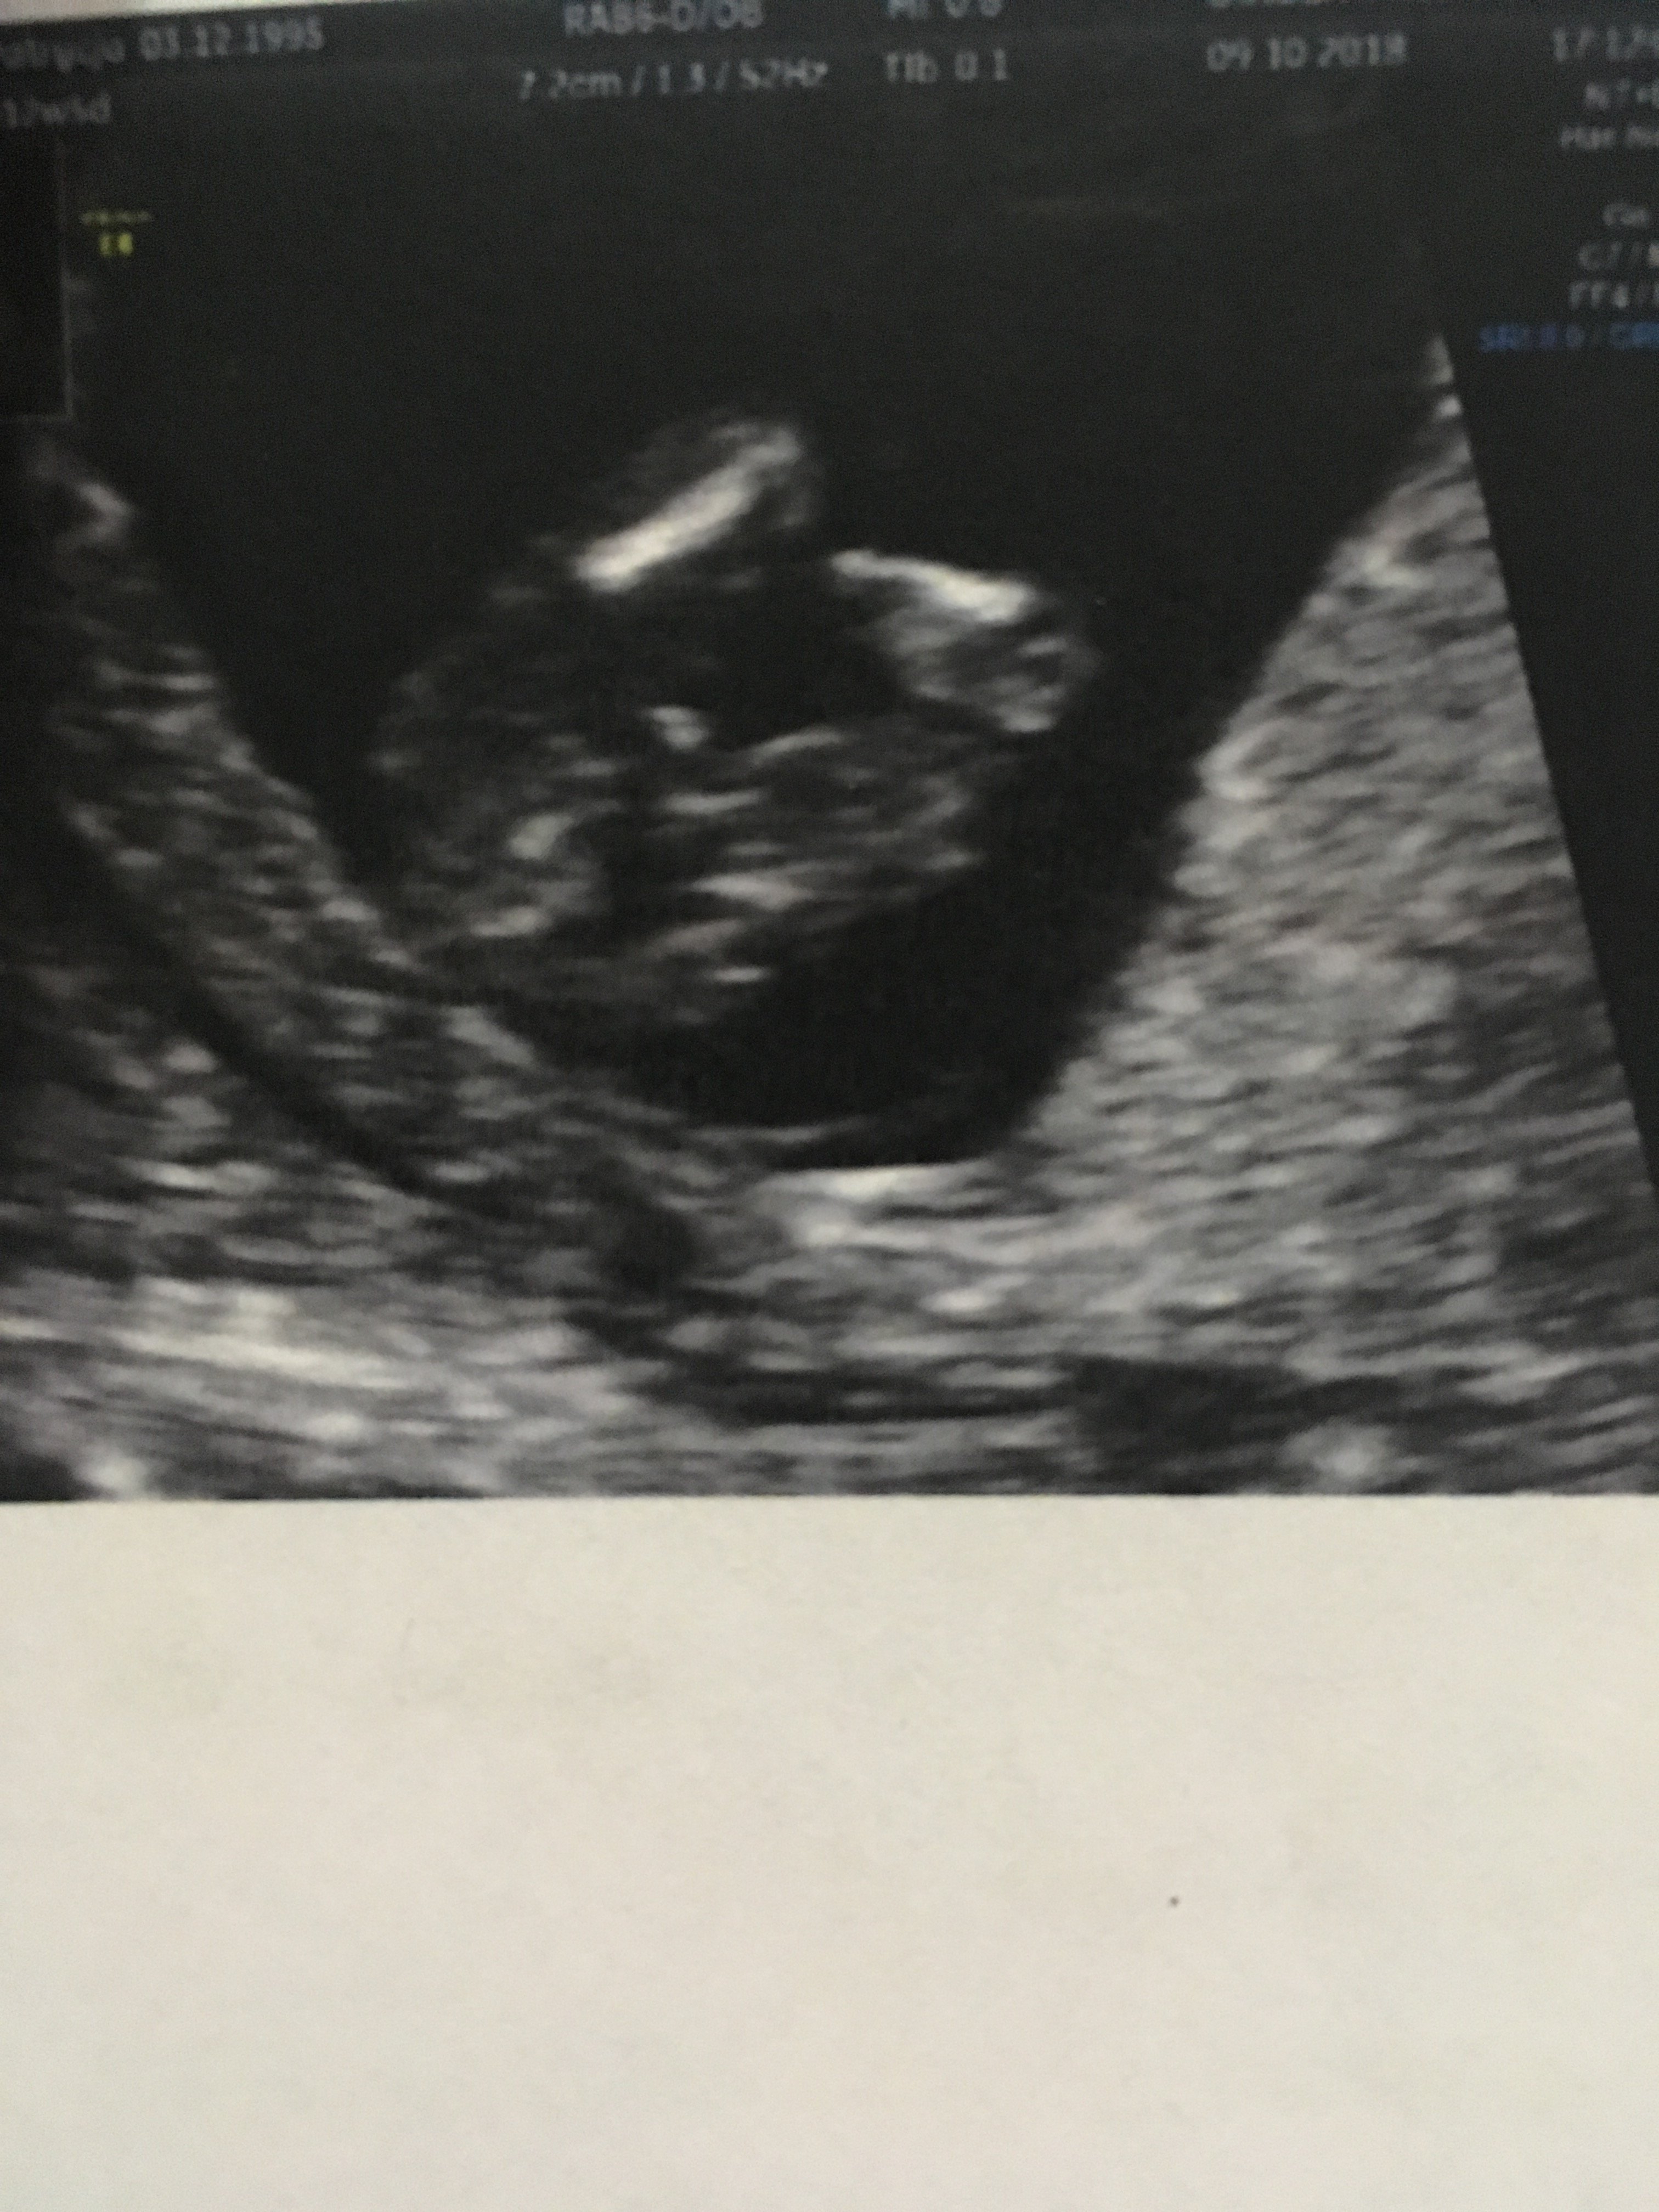

Witam w 19 tygodniu ciąży dowiedziałam się ze będę miała dziewczynkę w 20 tyg okazało się jednak , że to chłopak. Sama już nie wiem bo na jednym usg widać na pewno dziewuche a na drugim chłopca. Może to pempowina ?? Może ktoś mi pomoże rozwiązać ta zagadkę